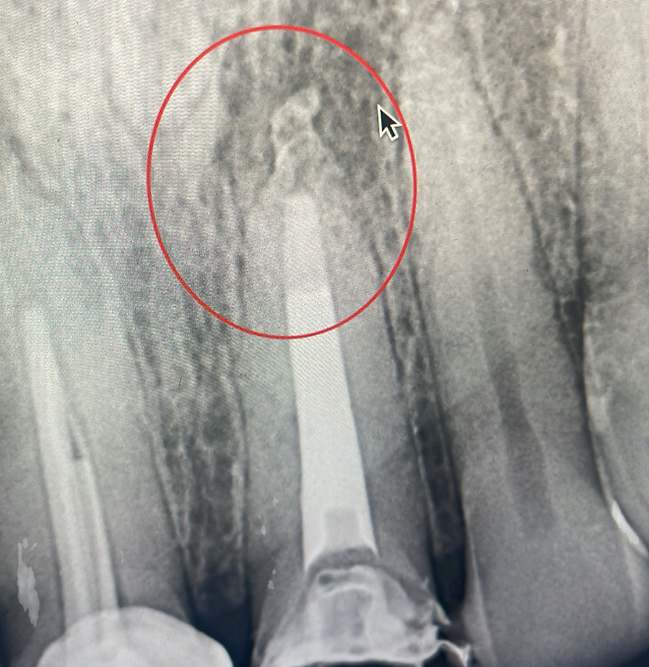

550 pesos mexicanosDa otra oportunidad a tu diente

Diagnostico PrevioTu segunda opción

Da otra oportunidad a tu diente

Tu segunda opción